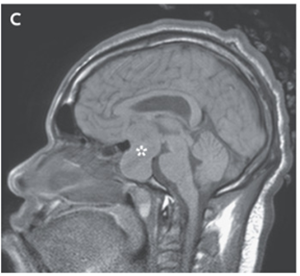

頭部MRIでは60mm×34mm×28mmの下垂体巨大腺腫を認めた。